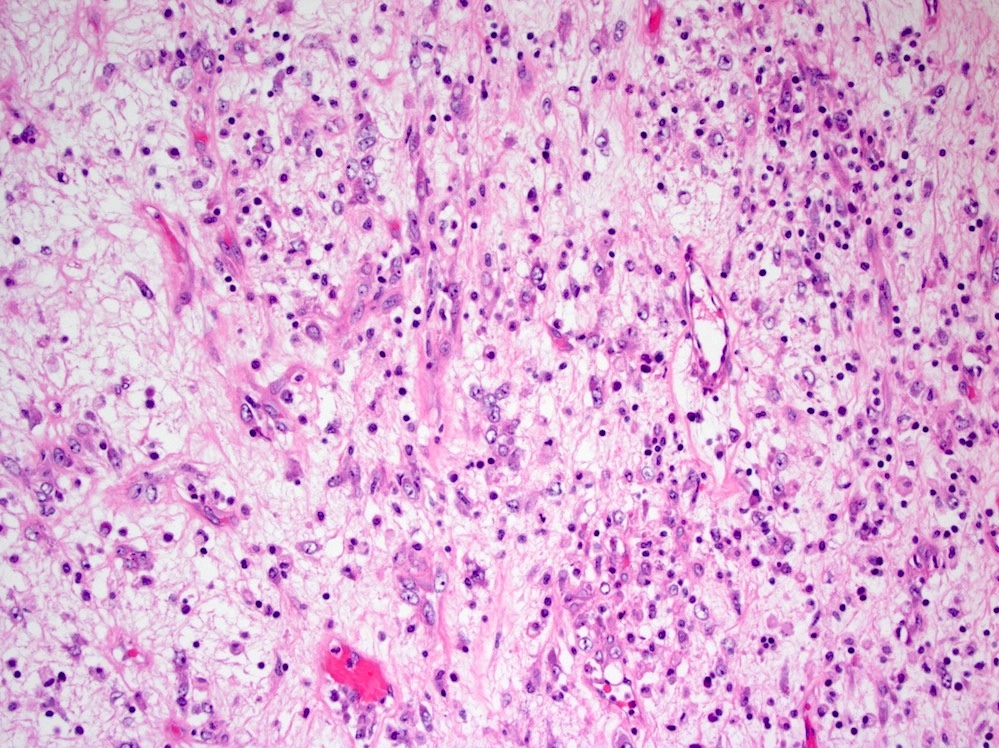

Microscopic (histologic) description

- Bland spindle cells with abundant amphophilic cytoplasm and variably prominent nucleoli

- Lymphoplasmacytic infiltrate with polyclonal plasma cells

- Background may show myxoid change or laminated / whorled fibrosis

- Epithelioid inflammatory myofibroblastic sarcoma: similar, except cells are more epithelioid, with large nucleoli

Microscopic (histologic) images

Contributed by Michael Feely, D.O.